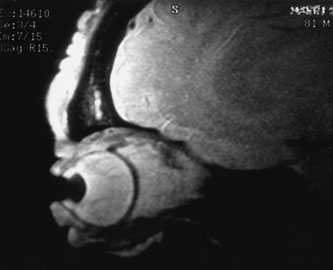

Investigations

If NFM is suspected, MRI should be ordered of the orbits and brain to exclude noncontiguous intracranial anomalies.93 Magnetic resonance imaging demonstrates the dilated cystic spaces with either a hypointense (lymphatic cyst) or hyperintense (hemorrhagic cyst) signal on T1-weighted images, and a hyperintense signal on T2-weighted images (Fig. 10, A&B).94Layering may be seen within the cysts if there has been a recent hemorrhage leaving unresorbed blood. The CT scans of patients with a deep NFM show low-density, poorly defined masses behind the orbital septum in the extraconal and intraconal spaces, which may indent the globe.3 Calcification within the mass (Fig. 11) and inhomogeneous enhancement of the rim and focal areas within the lesion may be seen that corresponds to abnormal endothelially lined channels.3 Enlargement of the bony orbit can occur, particularly with combined lesions.3,89 If the diagnosis is still unclear, ultrasonography can be performed. A cystic orbital mass is seen on B-scan. A-scan shows features of a solid, cellular tumor: low reflectivity, regular homogeneous internal structure, and marked sound attenuation through the mass.3,89 Standard pulsed Doppler ultrasound confirms no intrinsic flow within the lesions.

Fig. 10. A and B. No flow malformation of the orbit. Sagittal magnetic resonance imaging showing dilated cystic spaces hypointense to muscle on T1-weighted images (A) and hyperintense to muscle on T2-weighted images (B).